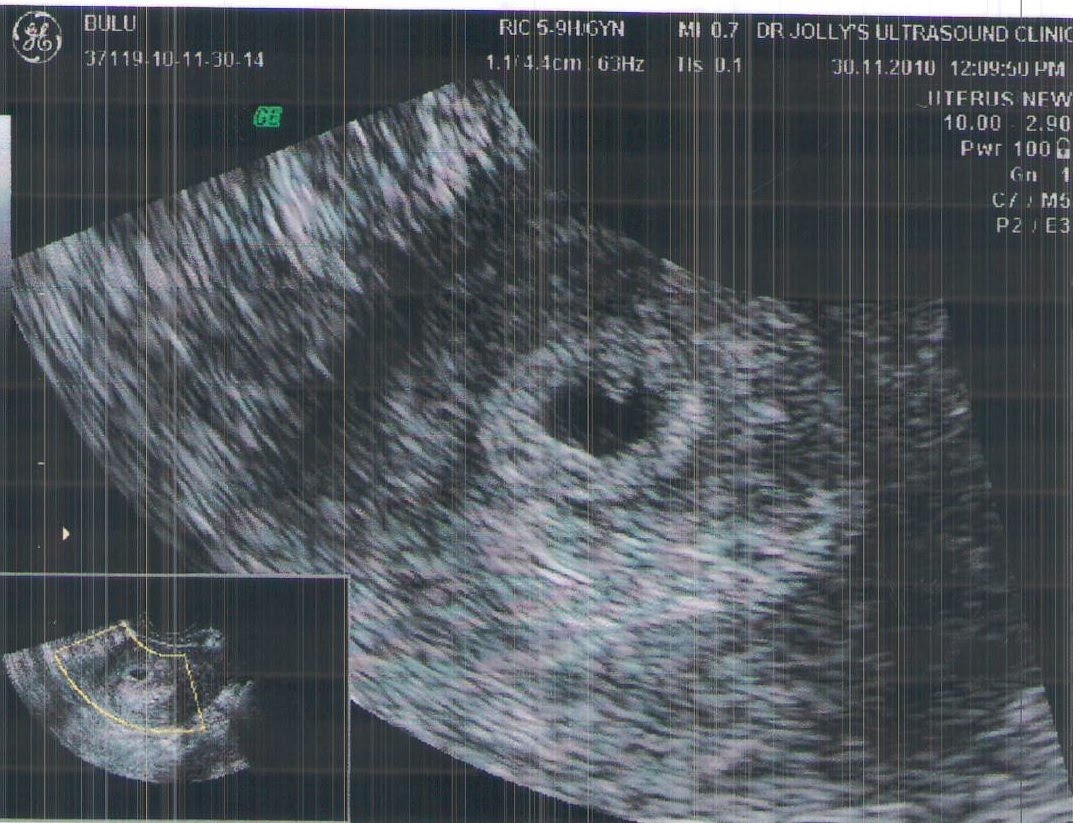

Our first result on about 16th November showed a good strong beta of 330...followed by the 30th November with a well defined gestational sac, 18th December we had a heartbeat! (whoo hoo!) and then 3rd January 2011 showed a good heartbeat and well developing fetus, we've just our 12 week scan today and here are the pics.....